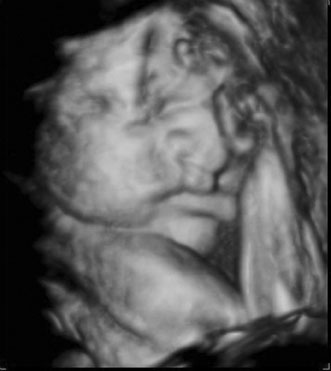

Maternal serum screening can identify pregnant women who are at an increased risk for having a baby with certain birth defects. Patient-specific risks for open spina bifida, Down syndrome and trisomy 18 (Edwards syndrome) (Fig. 1) can be determined by measuring the levels of certain proteins in maternal serum and combining those data with the patient's maternal age and clinical information.10 Women with a positive screen should be offered a definitive diagnostic test.

Fig. 1. Three-dimensional ultrasound showing typical pattern of trisomy 18. A clenched fist with the index finger overlapping the third and fourth fingers is distinctive of this disorder. Image courtesy of GE Medical Systems.